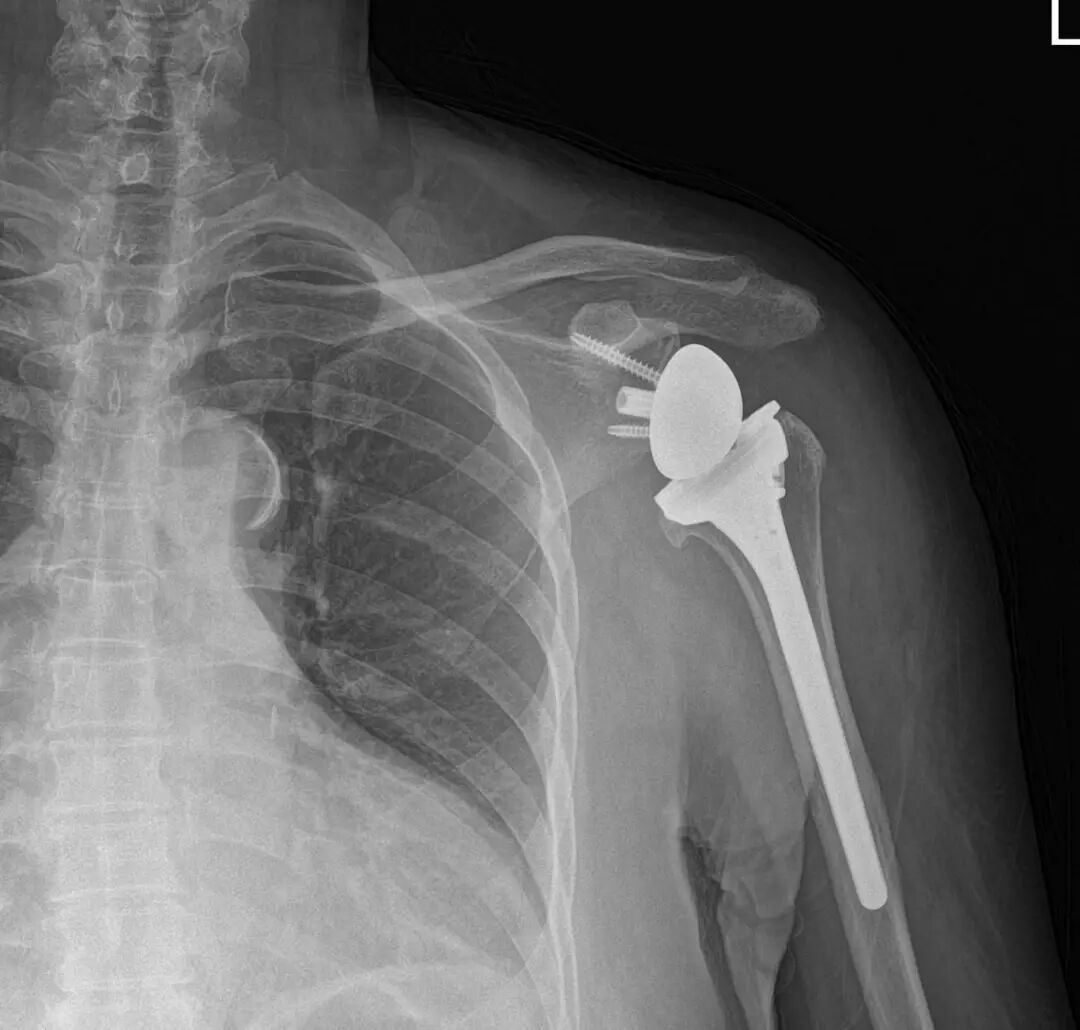

▲患者术后X片提示假体位置良好

程飚向施阿姨详细讲解了她的病情,普通的肩关节镜微创手术已无法达到理想的效果,需要为其更换一套全新的“肩关节动力系统”,即:反式人工肩关节置换术。完善术前相关准备后,在手术室护士和麻醉科医师的协助下,程飚为施阿姨成功施行了反肩关节置换手术。术后X片显示假体位置良好,当前施阿姨在康复科医师的指导下开始了康复锻炼。